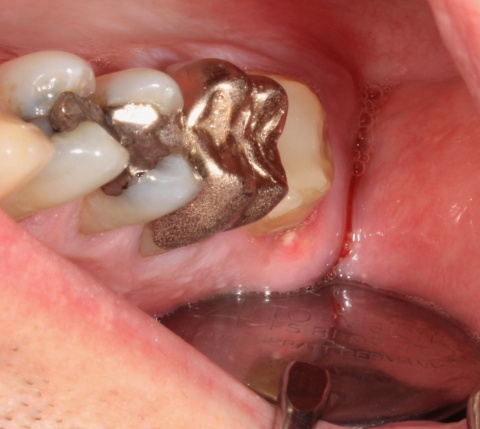

Eine Woche nach Wurzelfüllung wurde der Patient aufgrund von Schmerzen und einer Schwellung im disto-cervikalen Bereich des Zahnes 17 vorstellig (Abb. 8).

Zu diesem Zeitpunkt war der Zahn noch provisorisch mit Cavit® und einer Schicht Komposit verschlossen. Der Perkussionstest verlief negativ, jedoch zeigte sich noch eine Lockerung Grad I. Im Bereich des Vestibulums war weder eine Schwellung sicht- oder tastbar und dieser Bereich wies keine Druckdolenz auf. Ein Grund für diese Abszedierung kann in einer Traumatisierung des Gewebes durch die Kofferdamklammer mit einer bakteriellen Besiedlung zu sehen sein. Nach Infiltrationsanästhesie wurde der Abszess inzidiert und mit einer Povidon-Jod-Lösung (Betaisadona®, ADAG Pharma) gespült. Für eine Woche wurde adjuvant eine Antibiotikagabe verordnet (Clindamycin 400 mg). Vier Tage nach Inzision wurde der Patient zur Kontrolle einbestellt. Zu diesem Zeitpunkt war er beschwerdefrei und die Schwellung deutlich regredient. Im Rahmen dieser Nachkontrolle erfolgte die Entfernung der provisorischen Deckfüllung und eine Inspektion des Pulpencavums auf Risse oder Blutungen (Abb. 9). Diese Untersuchung fiel ohne pathologischen Befund aus, woraufhin eine definitive Deckfüllung appliziert werden konnte.